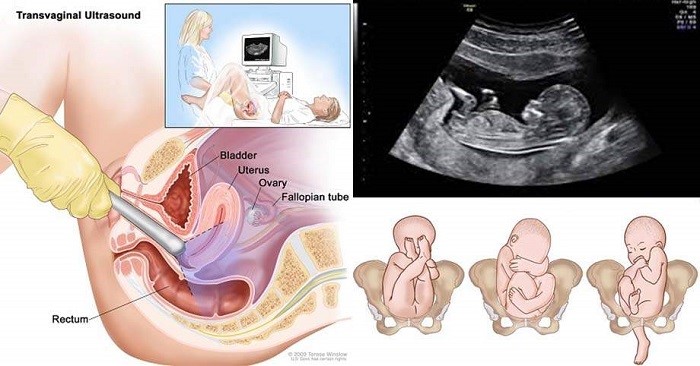

Siêu âm đầu dò là gì?

Siêu âm đầu dò có lẽ là 1 loại siêu âm không còn quá xa lạ với chị em phụ nữ. Nhất là với các bạn đã từng đi khám phụ khoa. Siêu âm đầu là loại siêu âm cực kì quan trọng, trong những tháng đầu mang thai.

Siêu âm đầu dò giúp bác sĩ kiểm tra được vị trí thai đã vào tử cung hay chưa, mẹ đã mang thai hay chưa, chuẩn đoán mang thai vào giai đoạn sớm nhất có thể. Vì những lần đầu tiên mang thai mẹ được bác sĩ thực hiện siêu âm đầu dò.

Ngoài siêu âm bụng, thai 12 tuần cũng có thể được bác sĩ chỉ định siêu âm đầu dò. Việc siêu âm đầu dò thường được chỉ định khi:

– Thai phụ có dấu hiệu chảy máu âm đạo bất thường

– Thai phụ bị viêm nhiễm phụ khoa

– Thai phụ có nguy cơ bị u hay ung thư cổ tử cung

– Thai phụ bị đau nhức vùng xương chậu thường xuyên

– Hay nhịp tim thai có bất thường

Những trường hợp này thường được bác sĩ khám thai chỉ định siêu âm đầu dò. Do đó, mẹ không cần quá lo lắng về việc thai 12 tuần siêu âm bụng hay đầu dò thì tốt hơn. Vì tùy từng trường hợp, bác sĩ sẽ ra quyết định thay mẹ. Mẹ chỉ cần làm theo chỉ định của bác sĩ để có kết quả khám thai chính xác nhất.